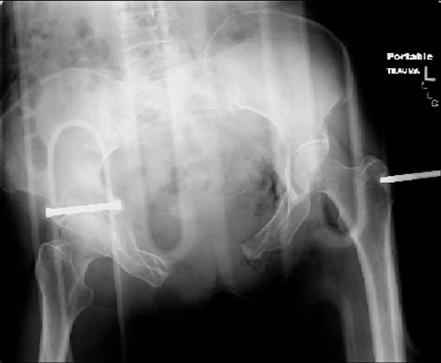

attached are images of a 70 year old female after peds versus car. her own car ran her over.

injuries are limited to the pelvis. left rami open and visible in a 10cm vertical laceration just lateral to left labia majora. wound is grossly clean. no vaginal and no urinary issues. CT scan shows widening of both SI joints anteriorly but I think this is vertically stable pattern.

pt treated that night with I/D and supra-acetabular frame to close the ring. consideration was given for SI screws bilateraly, but given time of night and other factors decision made not to proceed.

attached are several CT cuts. please let me know if you need more. the CT is pre-pelvic ex-fix placement.